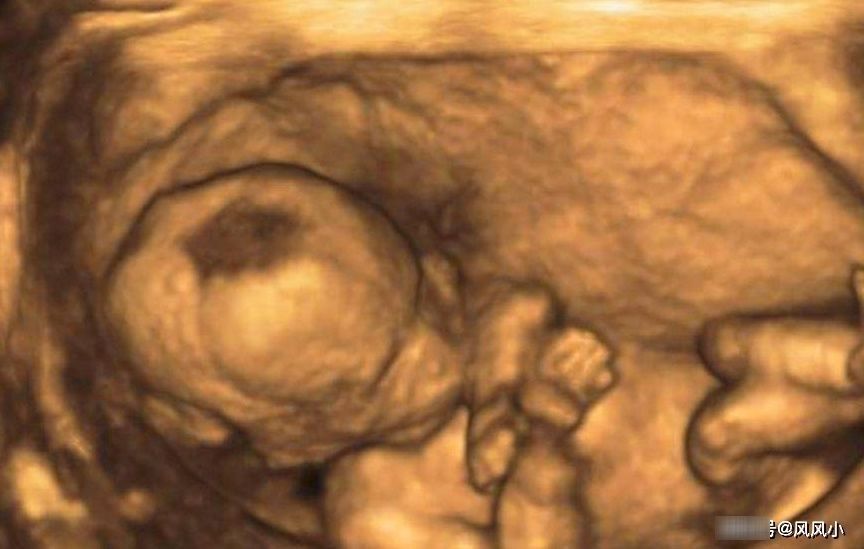

其实四维彩超跟三维差不多,就是彩超图片是彩色的,还能很清楚的看清宝宝在肚子的活动情况,小手和小脚在肚子里面动来动去的,伸伸懒腰,踢踢脚。各个地方都能清楚看到。但这得注意几个事项:做四维一般在24-28周做比较好。如果孕期太短,胎儿太小,各方面也没发育好,检查的不够全面,这个时候检查也纯属浪费钱,而且彩超也是有一定的辐射的,会伤害宝宝。孕期太大,胎儿太大在肚子里的活动空间小,无法伸展。就无法看清小孩的各个地方,所以做四维要选对时间,不然做了也是白费。